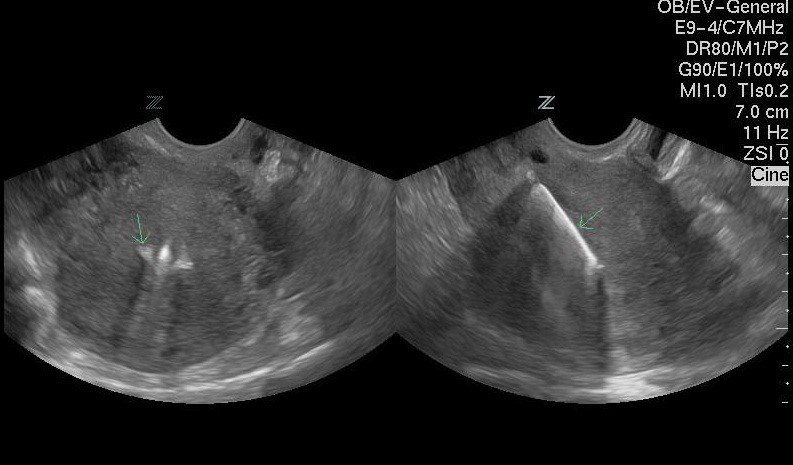

Процедура проводится под местной анестезией, перед этим доктор обязательно осматривает пациентку на наличие каких-либо патологий. Далее врач фиксирует шейку матки, чтобы избежать смещения, расширяет цервикальный канал. В него вводится сложенная спираль вместе с проводником, потом его удаляют, оставляя усики, за которые спираль будет впоследствии извлечена. С целью проверки правильности установки в течение 1–2 дней делают ультразвуковое исследование полости матки. Срок ношения ВМС составляет от трёх до пяти лет.

УЗИ необходимо для выявления возможных смещений спирали

Моя знакомая использовала внутриматочную спираль в качестве средства контрацепции. В течение нескольких месяцев после установки она испытывала неприятные тянущие ощущения в нижней части живота, сопровождающиеся незначительными кровянистыми выделениями. Через полгода у женщины нарушились менструации: вместо 3–5 дней они стали длиться более 12 суток. Девушка обратилась к врачу, в клинике ей сделали ультразвуковое исследование, которое показало, что спираль сместилась и повредила стенку матки. Пришлось немедленно удалить это средство контрацепции, чтобы избежать осложнений, а также провести операцию по устранению перфорации. После выписки пострадавшая подобрала для себя другой метод предохранения.